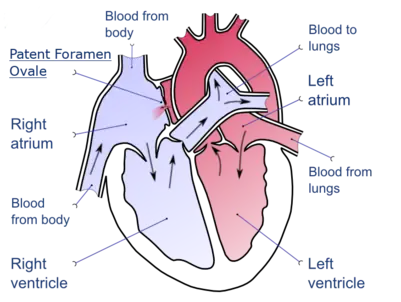

Patent foramen ovale

A patent foramen ovale (PFO) is a remnant opening of the fetal foramen ovale, which often closes after a person's birth. This remnant opening is caused by the incomplete fusion of the septum primum and the septum secundum; in healthy hearts, this fusion form the fossa ovalis, a portion of the interatrial septum which corresponds to the location of the foramen ovale in the fetus.[7] In medical use, the term "patent" means open or unobstructed.[8] In about 25% of people, the foramen ovale does not close, leaving them with a PFO or at least with what some physicians classify as a "pro-PFO", which is a PFO that is normally closed, but can open under increased right atrial pressure. On echocardiography, shunting of blood may not be noted except when the patient coughs.

PFO is linked to stroke, sleep apnea, migraine with aura, cluster headache, decompression sickness, Raynaud's phenomenon, hyperventilation syndrome, transient global amnesia (TGA), and leftsided carcinoid heartdisease (mitral valve). No cause is established for a foramen ovale to remain open instead of closing, but heredity and genetics may play a role.[9][10] In rats research showed a link to the amount of Cryptosporidium infestation and the number of newborn rats that failed to close their foramen ovale. PFO is not treated in the absence of other symptoms.

The mechanism by which a PFO may play a role in stroke is called paradoxical embolism. In the case of PFO, a blood clot from the venous circulatory system is able to pass from the right atrium directly into the left atrium via the PFO, rather than being filtered by the lungs, and thereupon into systemic circulation toward the brain.[11][12] Also multiple substances -including the prothrombotic agent serotonin- are shunted bypassing the lungs. PFO is common in patients with an atrial septal aneurysm (ASA), a much rarer condition, which is also linked to cryptogenic (i.e., of unknown cause) stroke.[13]

PFO is more common in people with cryptogenic stroke than in those with a stroke of known cause.[14] While PFO is present in 25% in the general population, the probability of someone having a PFO increases to about 40 to 50% in those who have had a cryptogenic stroke, and more so in those who have a stroke before the age of 55.[11] Treatment with anticoagulant and antiplatelet medications in this group appear similar.[15]